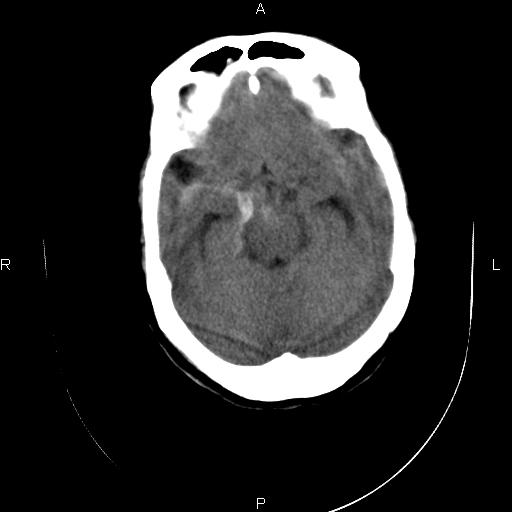

标题: CT20052:女76岁既往偶有头疼。

近三天来阵发性头剧疼 头晕加重。考虑蛛血?双额叶颅板下低密度是否为蛛网膜囊肿?请老师们指教指教!

1、蛛网膜下腔出血;

2、脑萎缩,双额叶颅板下低密度为增宽的蛛网膜下腔。

2、双侧额部硬膜下积液;

3、轻度脑积水(三脑室球形扩大),扩大的侧脑室颞角和前角都有张力。

1)蛛网膜下腔出血。2)双侧侧脑室少量出血。3)双侧额部硬膜下积液。4)脑积水。

1、蛛网膜下腔出血。

2、双侧额骨颅骨内板下的带状低密度影,不是增宽的蛛网膜下腔。依据:本病人本身有蛛网膜下腔出血,双侧额叶表面有一带状高密度影,那才是有出血的蛛网膜下腔。前面的带状低密度影(额骨内板下)是硬膜下积液表现,其内没有出血迹象,与出血的蛛网膜下腔界限清晰。